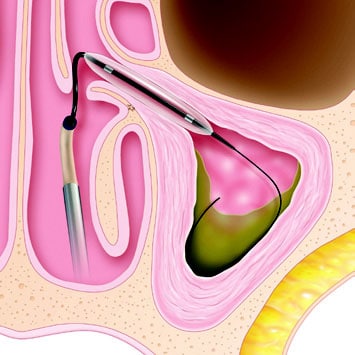

Balloon sinuplasty is typically performed in an outpatient setting. You’ll usually be given an oral sedative and a local anesthetic to help keep you comfortable while your ENT surgeon uses an endoscope to help guide the balloon catheter into your sinuses. The balloon is then inflated to enlarge the sinus opening and widen the walls of the nasal passages. The goal is to enlarge your sinus opening to improve drainage and airflow permanently.

During the surgery, a saline solution is often sprayed into the sinuses to flush out mucus and other debris; the catheter is then removed. Up to 95% of patients report a significant improvement in sinus symptoms following this procedure.